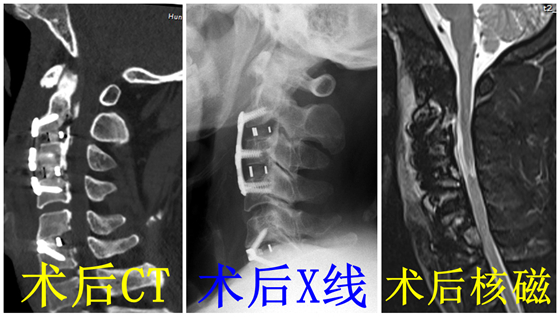

在充分的术前准备基础上,湘雅常德医院骨科团队凭借丰富的脊柱外科经验,在吴天定副教授指导下,成功攻克了这一高难度手术。术中,团队运用精准解剖技术,顺利将骨化物复合体前移,实现有效减压。术后影像学检查证实,患者颈椎序列恢复良好,骨化物复合体前移位置精准,脊髓压迫完全解除,四肢麻木症状显著改善。患者在术后短时间内即可佩戴支具下床活动,目前已康复出院。